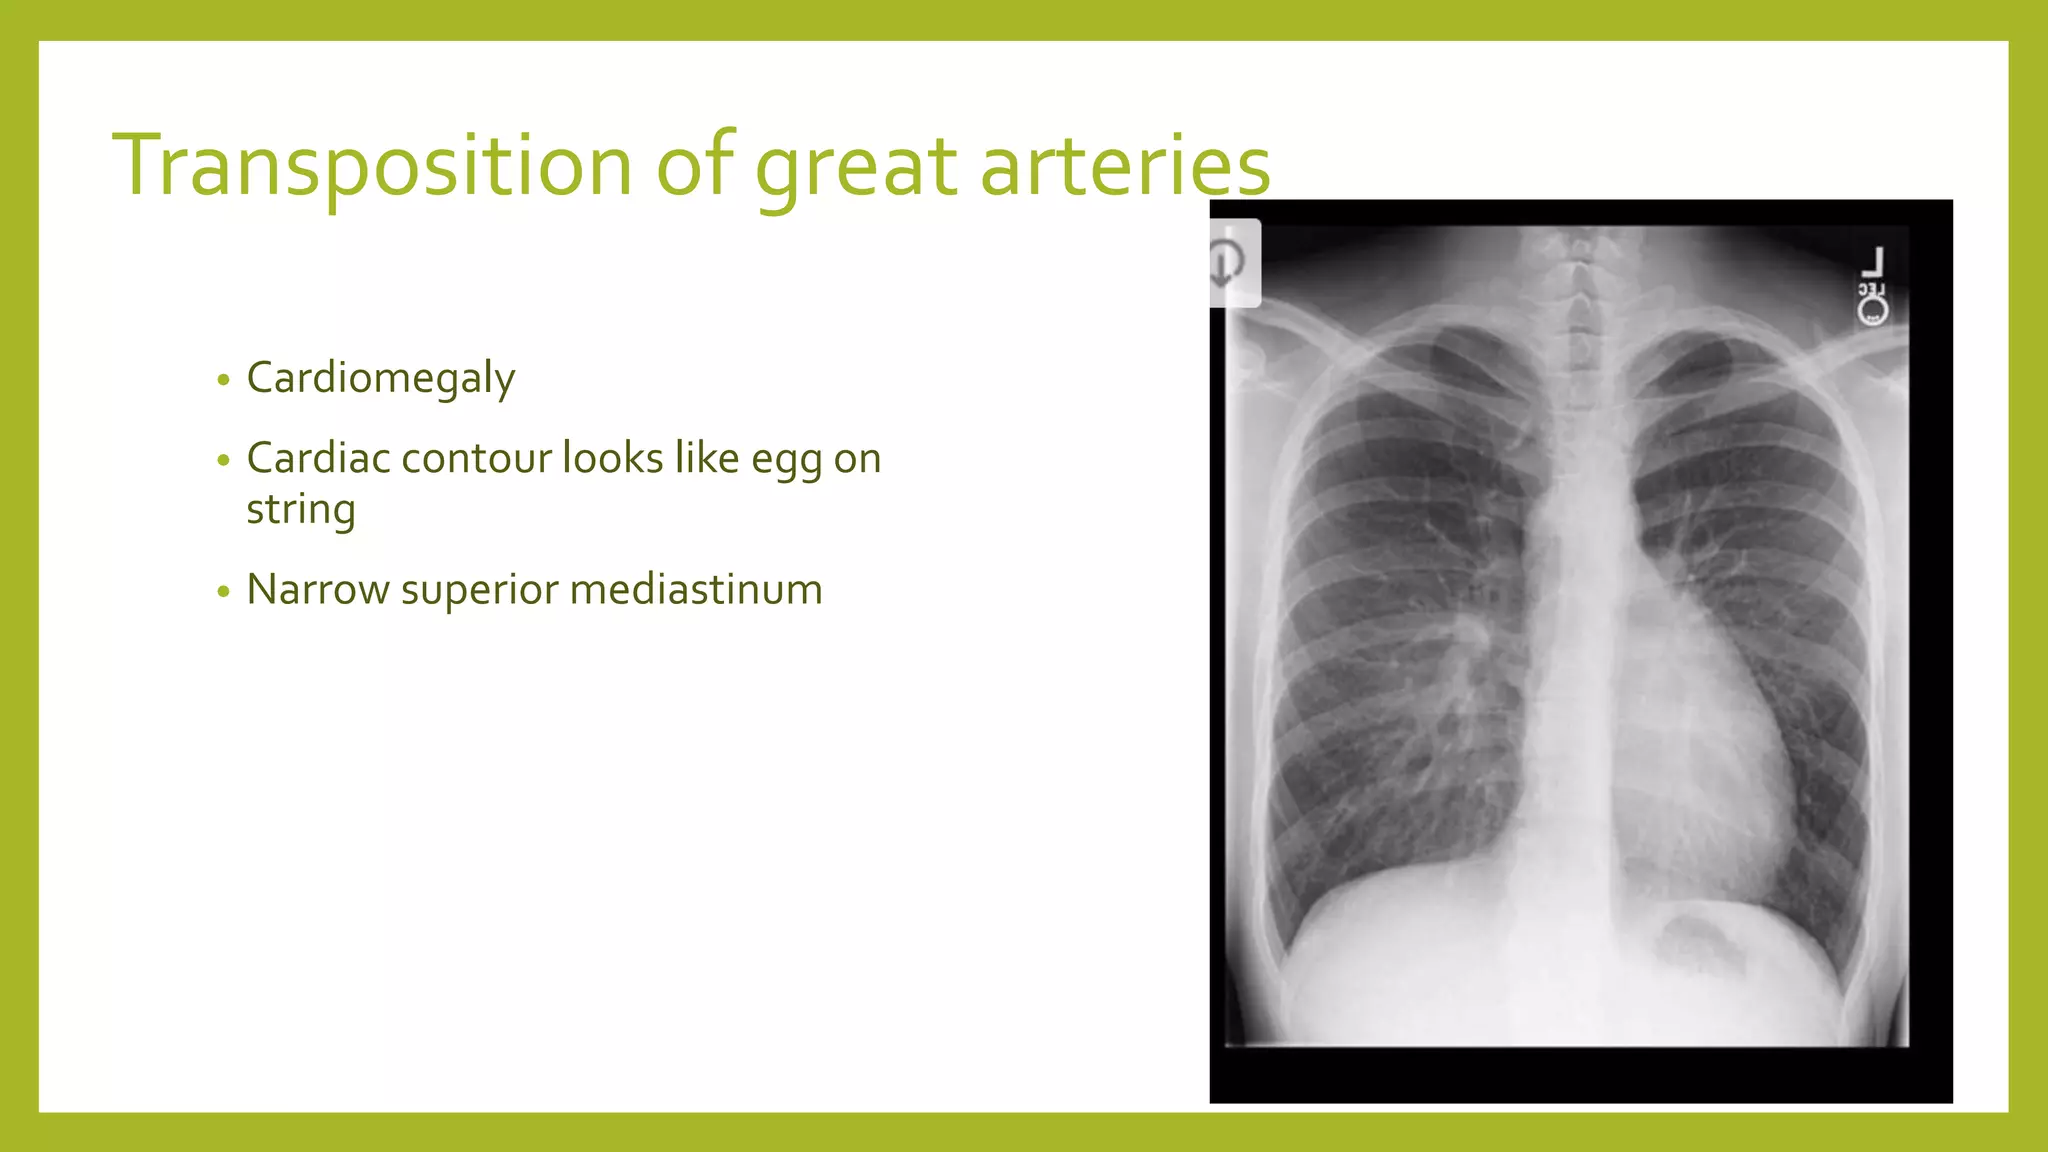

The document provides guidance on approaching and interpreting chest x-rays (CXR). It outlines steps to check the name, date and quality of the film, systematically scan the CXR looking for abnormalities, and determine if the lungs appear too white or black. Specific signs are described to help localize abnormalities, including the cardiac silhouette sign and pleural effusion signs. Examples are given of respiratory distress syndrome, tetralogy of fallot, transposition of great arteries, and total anomalous pulmonary venous return. The take home message is to summarize positive findings, compare to prior CXRs if available, and confirm findings with a radiologist.